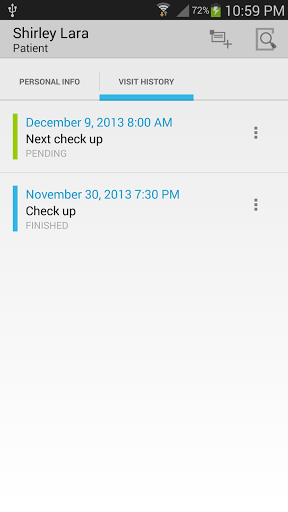

• Voir la visite du patient / antécédents médicaux